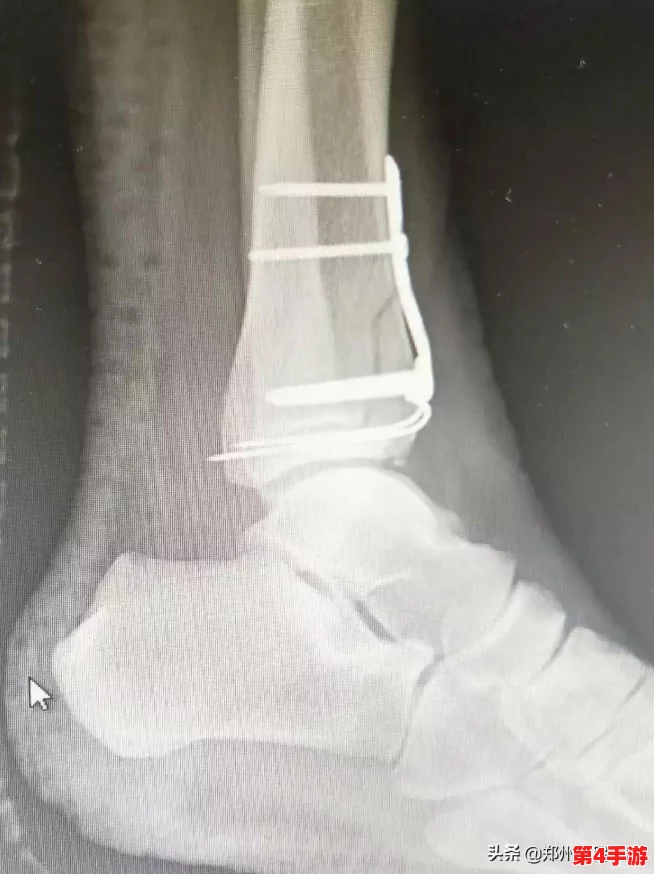

“疯批父子骨科”不仅仅是一个幽默故事,它还让人们对医学产生了更深的理解。在父亲的角色中,医术的严谨和人际关系的幽默形成了鲜明对比。通过故事,读者不仅可以看到疾病的处理与医疗技术的讲解,还能感受到医生在生活中轻松幽默的一面。这种转变让医学不再显得那么冷酷,也让我们更加贴近生活。